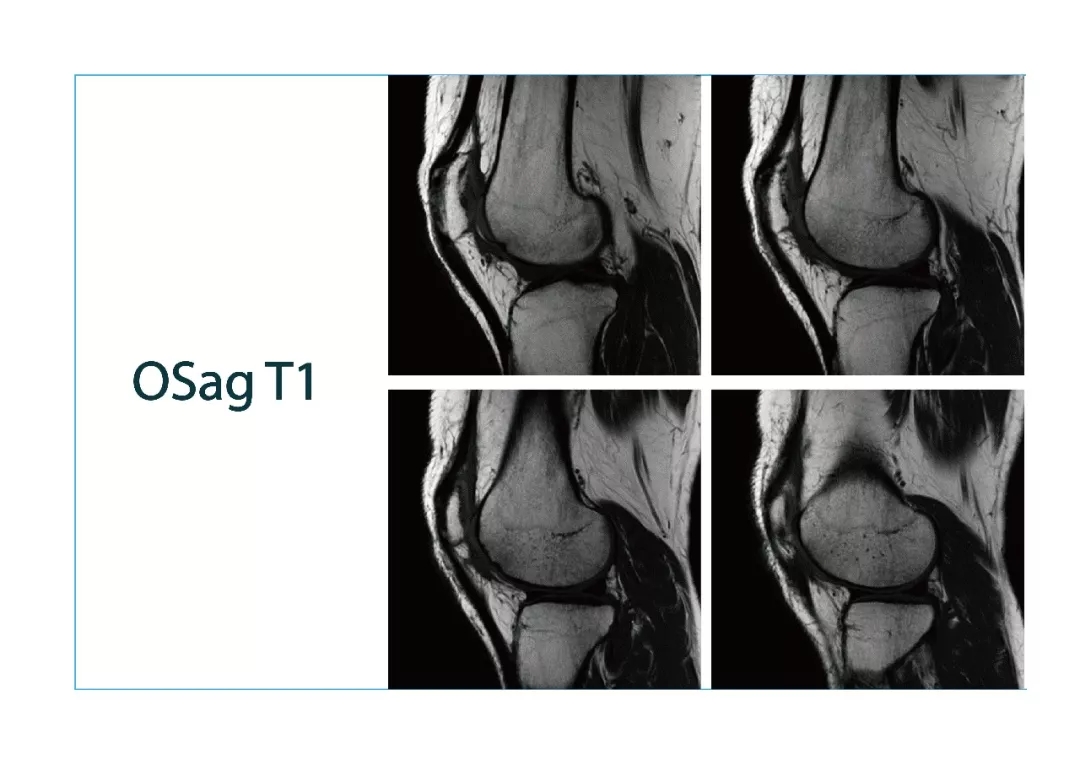

【朗润影像档案】20180119磁共振影像病例结果讨论